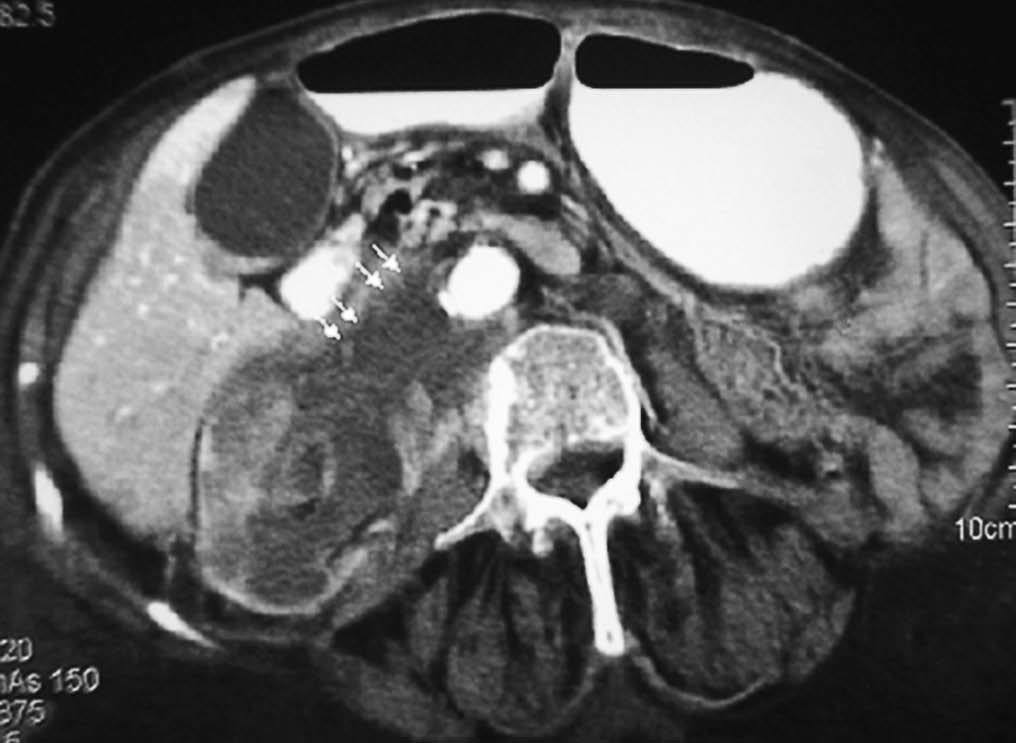

Fig. 20--Linfoma duodenal. (A) Ecografía. (B) Tomografía computarizada con contraste intravenoso que muestra un engrosamiento circunferencial de la pared duodenal (D) con adenopatías mesentéricas y retroperitoneales (flechas).